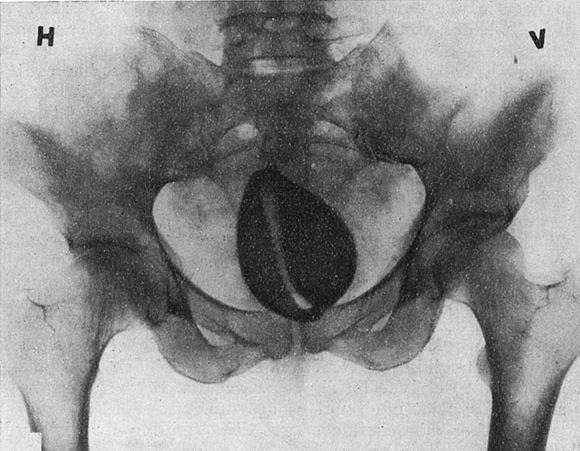

Vi visste ikke riktig hvad dette skulde være. Vi tenkte naturligvis først på et forkalket myom og slett ikke på fremmedlegeme. Men før vi foretok nogen vaginal inspeksjon, sendte vi patienten til røntgenundersøkelse. Dagen efter var der til visitten lagt frem et høist eiendommelig røntgenogram. Det viste en massiv skygge av et stort legeme i det lille bekken som med en smal munnspalte og en lang tannrad gren mot oss. Likheten med et konkylie var slående.